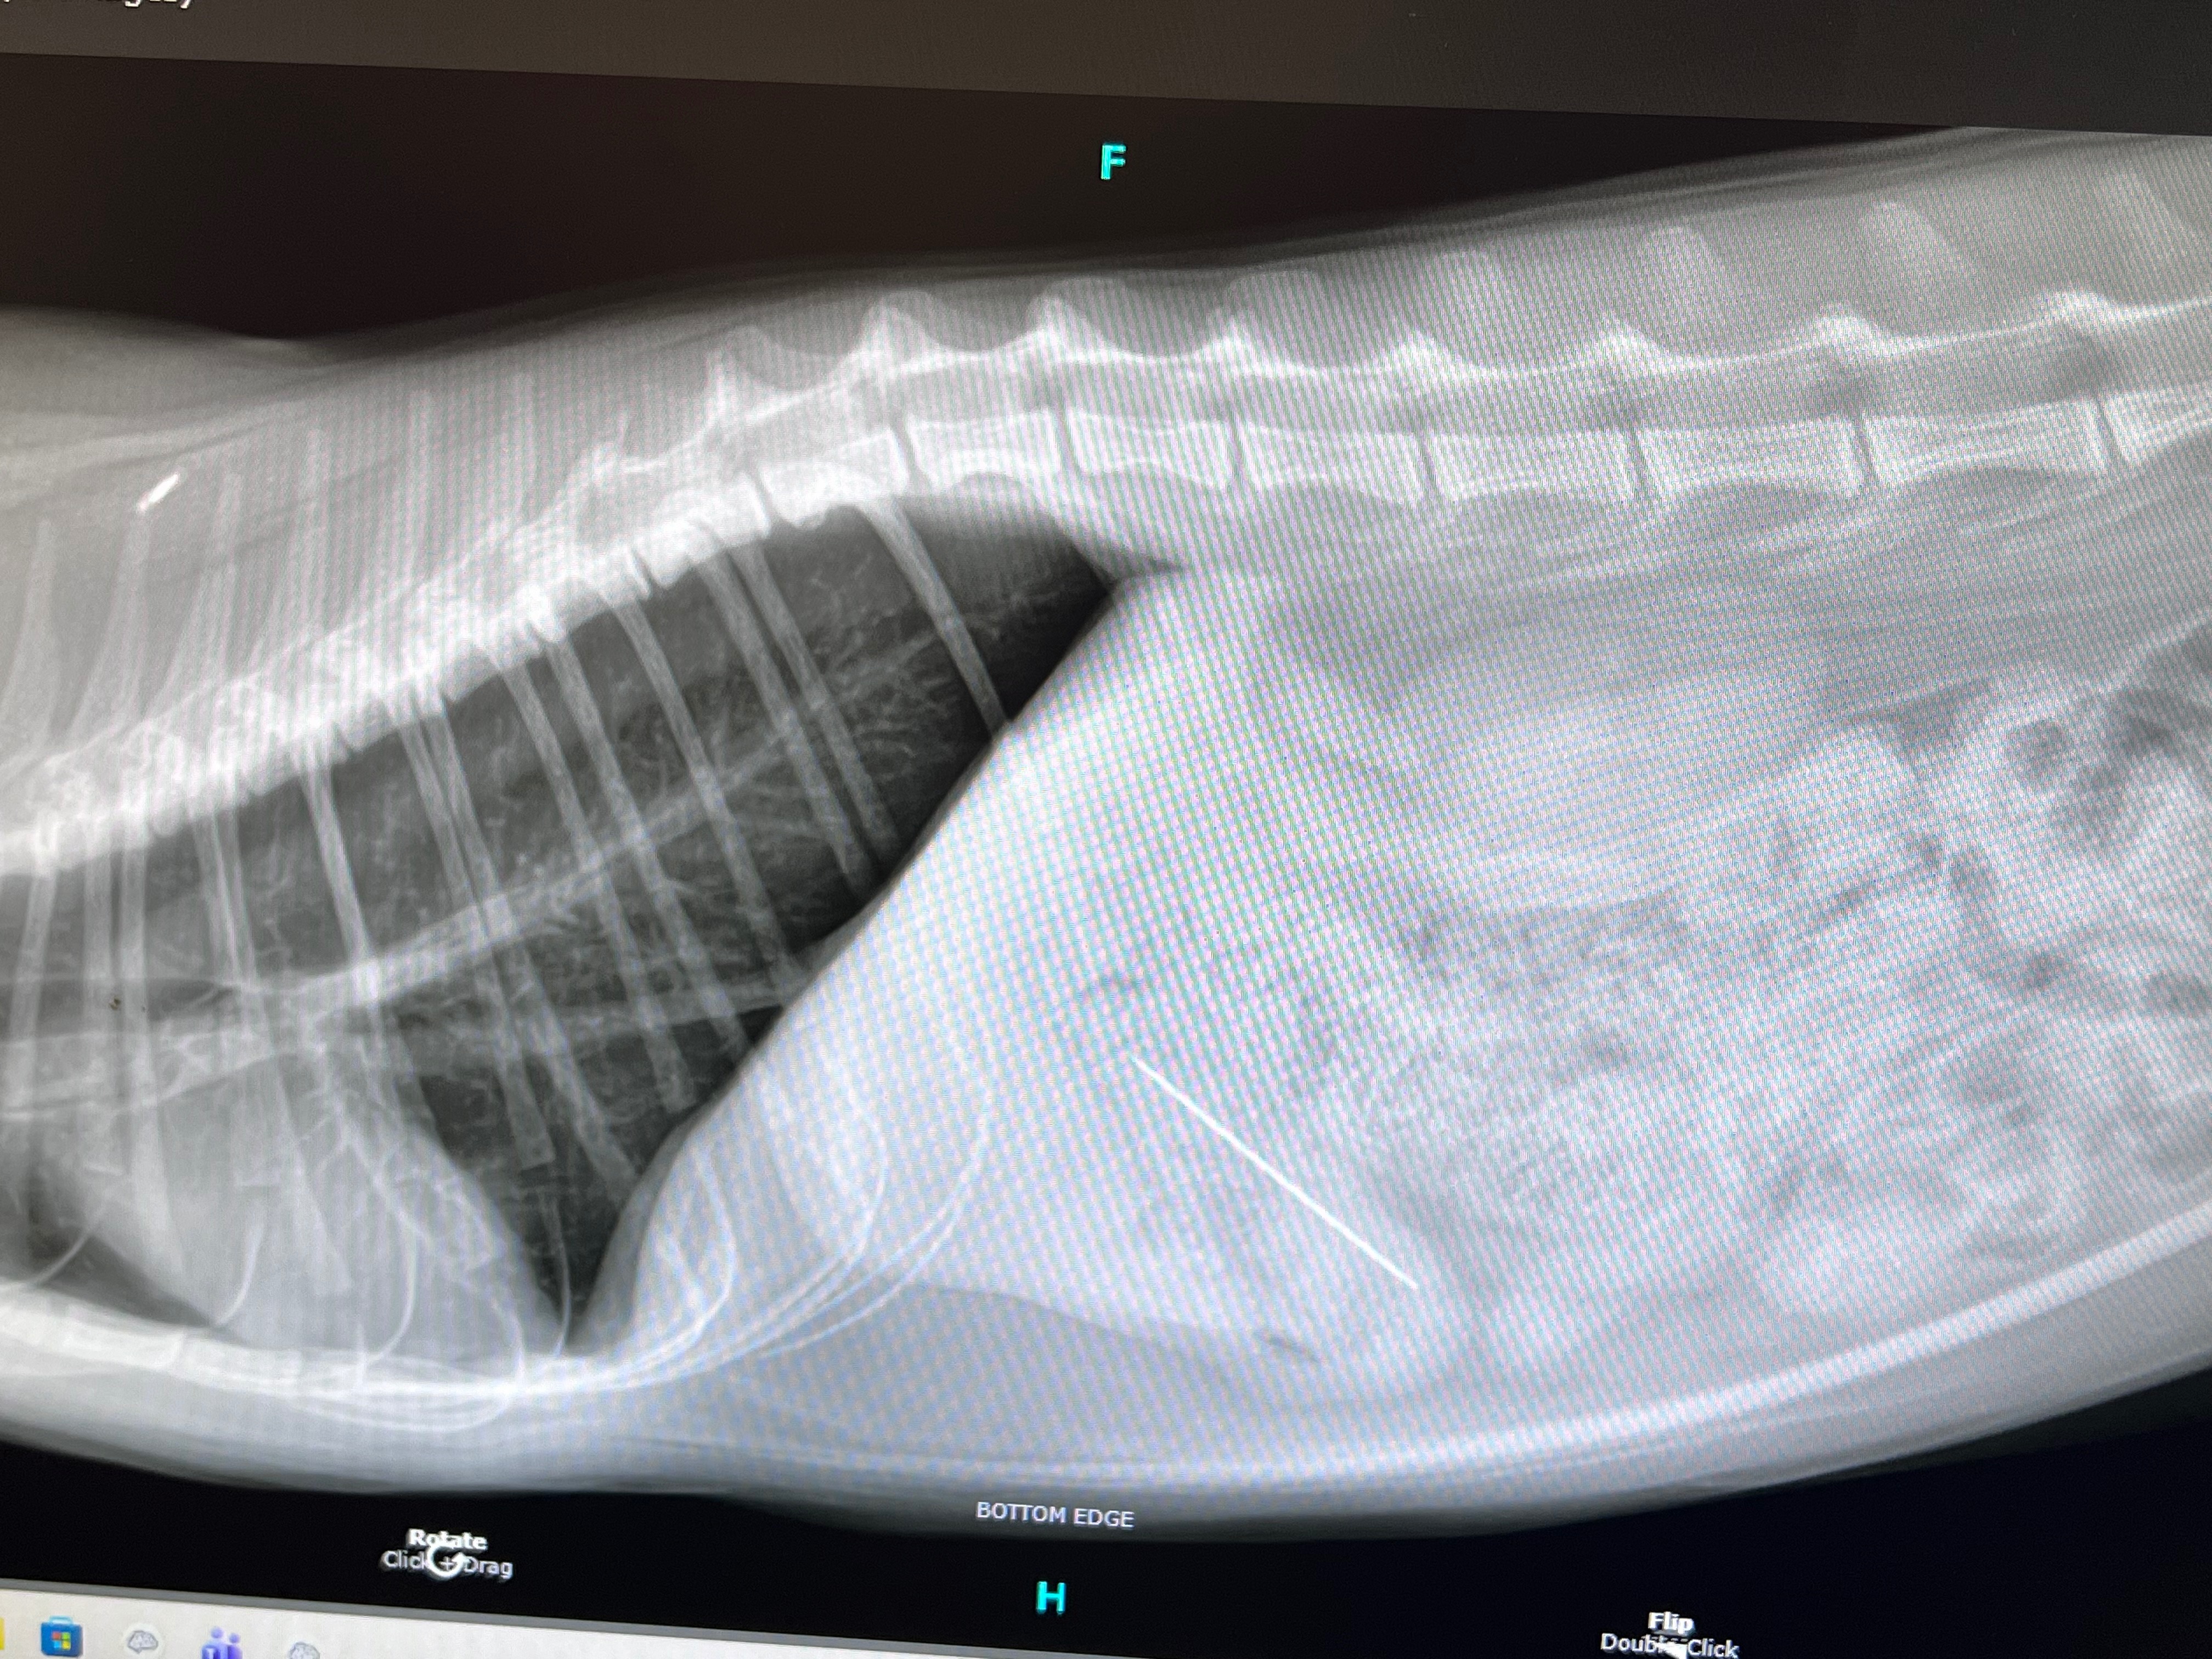

We called the nearest emergency vet in advance and were quoted with a $215 initial examination fee, we drove over and checked in. She needed to get X-rays done which were $346.50, the X-rays showed the needle was lodged at the entrance of her stomach.